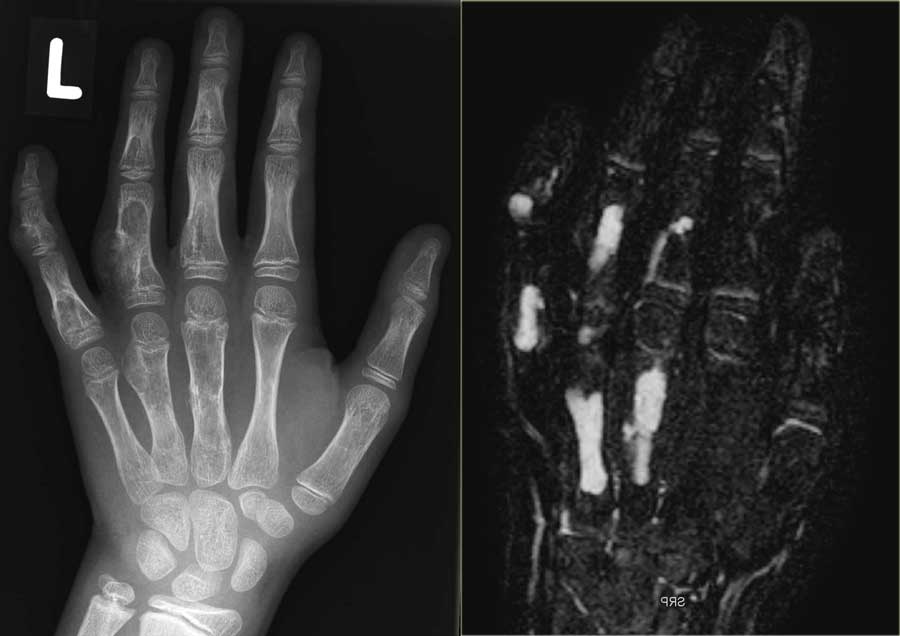

Enchondroma (5)

On the left a patient with multiple eccentric lytic lesions in the metacarpal bones and phalanges of the left hand.

On T2-WI with FS there is homogeneous high SI of the lesions.

On the left another patient with multiple well-defined lytic lesions in a central and eccentric localisation in the phalanges.

On the right the MR of a different patient with multiple lobulated chondroid lesions with high SI on T2-WI with fatsat.